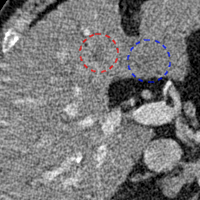

To show the denoising effect of the selected networks, we took two representative slices as shown in Figs. 5 and 7. And Figs. 6 and 8 are the zoomed regions-of-interest (ROIs) marked by the red rectangles in Figs. 5 and 7. All the networks demonstrated certain denoising capabilities. However, CNN-MSE blurred the images and introduced waxy artifacts as expected, which are easily observed in the zoomed ROIs in Figs. 6e and 8e. WGAN-MSE was able to improve the result of CNN-MSE by avoiding over-smooth but minor streak artifacts can still be observed especially compared to CNN-VGG and WGAN-VGG. Meanwhile, using WGAN or GAN alone generated stronger noise (Figs. 6g and 8g) than the other networks enhanced a few white structures in the WGAN/GAN generated images, which are originated from the low dose streak artifact in LDCT images, while on the contrary the CNN-VGG and WGAN-VGG images are visually more similar to the NDCT images. This is because the VGG loss used in CNN-VGG and WGAN-VGG is computed in a feature space that is trained previously on a very large natural image dataset [48]. By using VGG loss, we transferred the knowledge of human perception that is embedded in VGG network to CT image quality evaluation. The performance of using WGAN or GAN alone is not acceptable because it only maps the data distribution from LDCT to NDCT but does not guarantee the image content correspondence. As for the lesion detection in these two slices, all the networks enhance the lesion visibility compared to the original noisy low dose FBP images as noise is reduced by the different approaches.

As for iterative reconstruction technique, the reconstruction results depend greatly on the choices of the regularization parameters. The implemented dictionary learning reconstruction (DictRecon) result gave the most aggressive noise reduction effect compared to the network outputs as a result of strong regularization. However, it over-smoothed some fine structures. For example, in Fig. 8, the vessel pointed by the green arrow was smeared out while it is easily identifiable in NDCT as well as WGAN-VGG images. Yet, as an iterative reconstruction method, DictRecon has its advantage over post-processing method. As pointed by the red arrow in Fig 8, there is a bright spot which can be seen in DictRecon and NDCT images, but is not observable in LDCT and network processed images. Since the WGAN-VGG image is generated from LDCT image, in which this bright spot is not easily observed, it is reasonable that we do not see the bright spot in the images processed by neural networks. In other words, we do not want the network to generate structure that does not exist in the original images. In short, the proposed WGAN-VGG network is a post-processing method and information that is lost during the FBP reconstruction cannot easily be recovered, which is one limitation for all the post-processing methods. On the other hand, as an iterative reconstruction method, DictRecon algorithm generates images from raw data, which has more information than the post-processing methods.